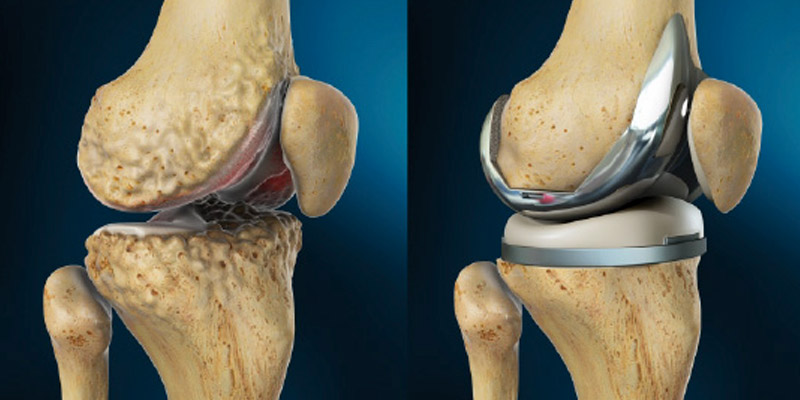

第四阶段:严重骨关节炎

在这个高级阶段,关节间隙显著减小,导致慢性疼痛和活动受限。主要的治疗选择是:

- 全膝关节置换手术:在其他治疗不再缓解症状的情况下,这种手术程序会用人工关节替换受损的关节。

- 术后物理疗法:手术后的康复锻炼帮助您恢复力量和活动。